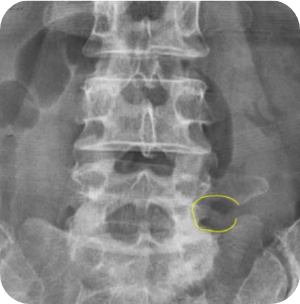

- 극외측협착증

- 척추분리증성 전방전위증